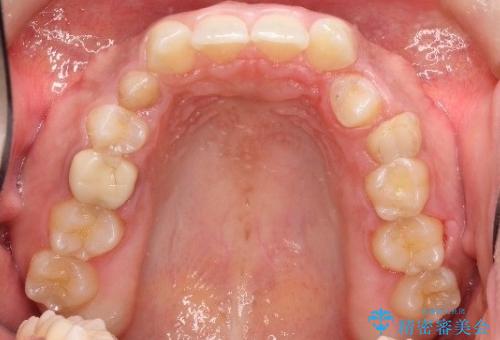

- 後続永久歯が欠損した患者様です。

矯正治療にて歯並びを改善したのち、インプラントにて咬合回復を行う治療計画としました。

捻転が強い部分だけはワイヤーの部分矯正で対応しております。